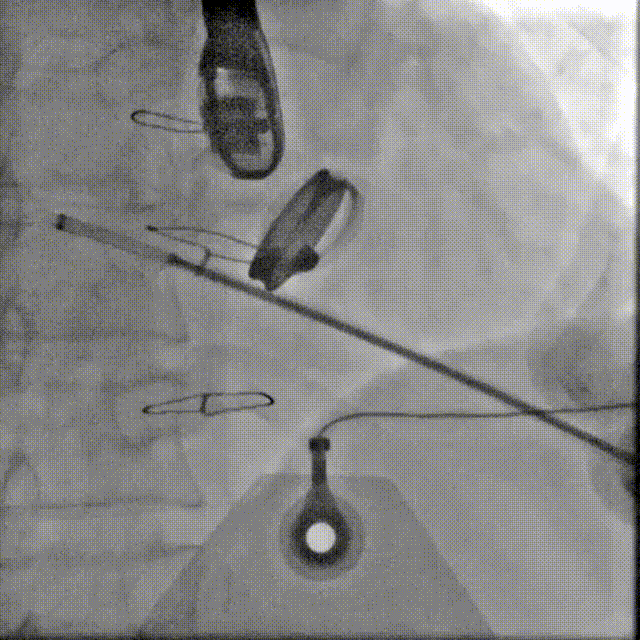

手术操作

1.患者平卧位,食道超声检查瓣周漏位置及大小,并引导穿刺心尖,选择7F鞘管通过10点位置瓣周漏口,将单弯导管送入左心室,置换超硬导丝至左心室,选择12-14mmPDAO封堵10点位漏口。

3.选择7F鞘管通过1-2点位置瓣周漏,彩超显示鞘管对瓣周漏口的影响较小,结合漏口大小,选择14-16mmPDAO封堵此处漏口。

术后封堵器形态位置